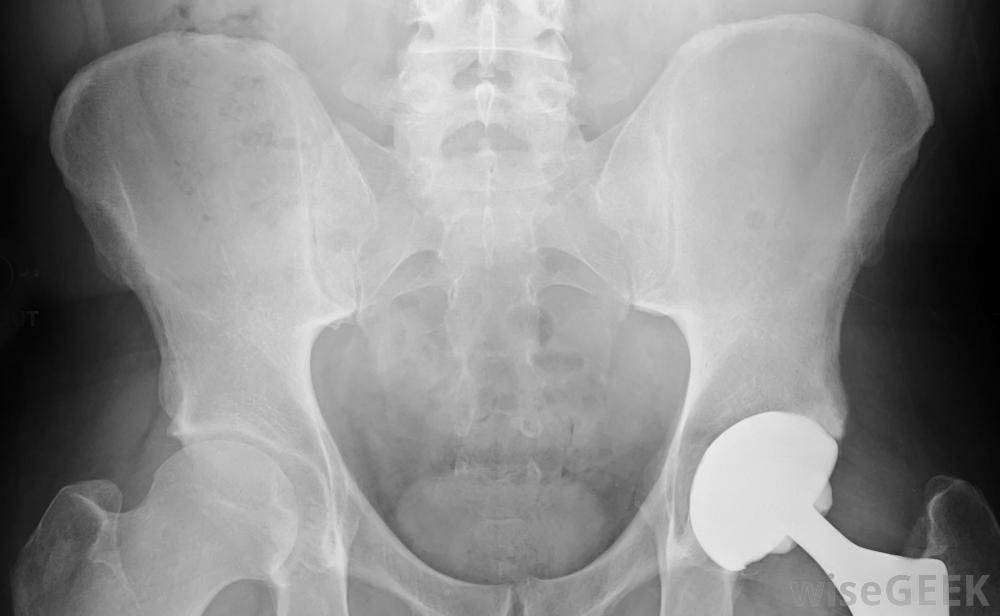

人造髖關節是一種假肢裝置。